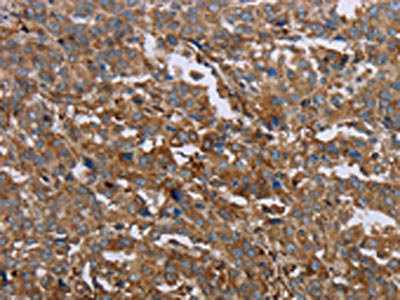

The image on the left is immunohistochemistry of paraffin-embedded Human liver cancer tissue using CSB-PA138466(GCK Antibody) at dilution 1/40, on the right is treated with fusion protein. (Original magnification: ×200)